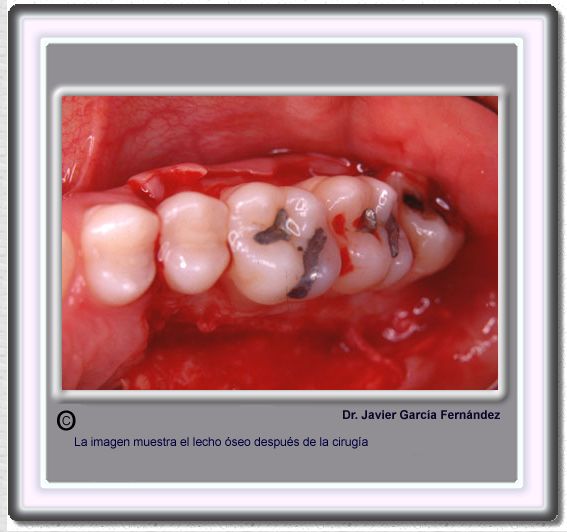

image 700